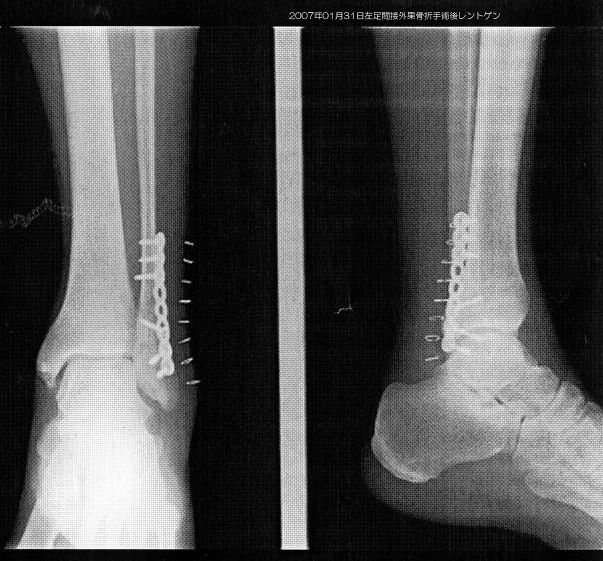

手術直後のレントゲン